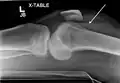

Fractura de meseta tibial leve en vista con Rayos X AP en la rodilla

Una fractura de meseta tibial vista con rayos-X